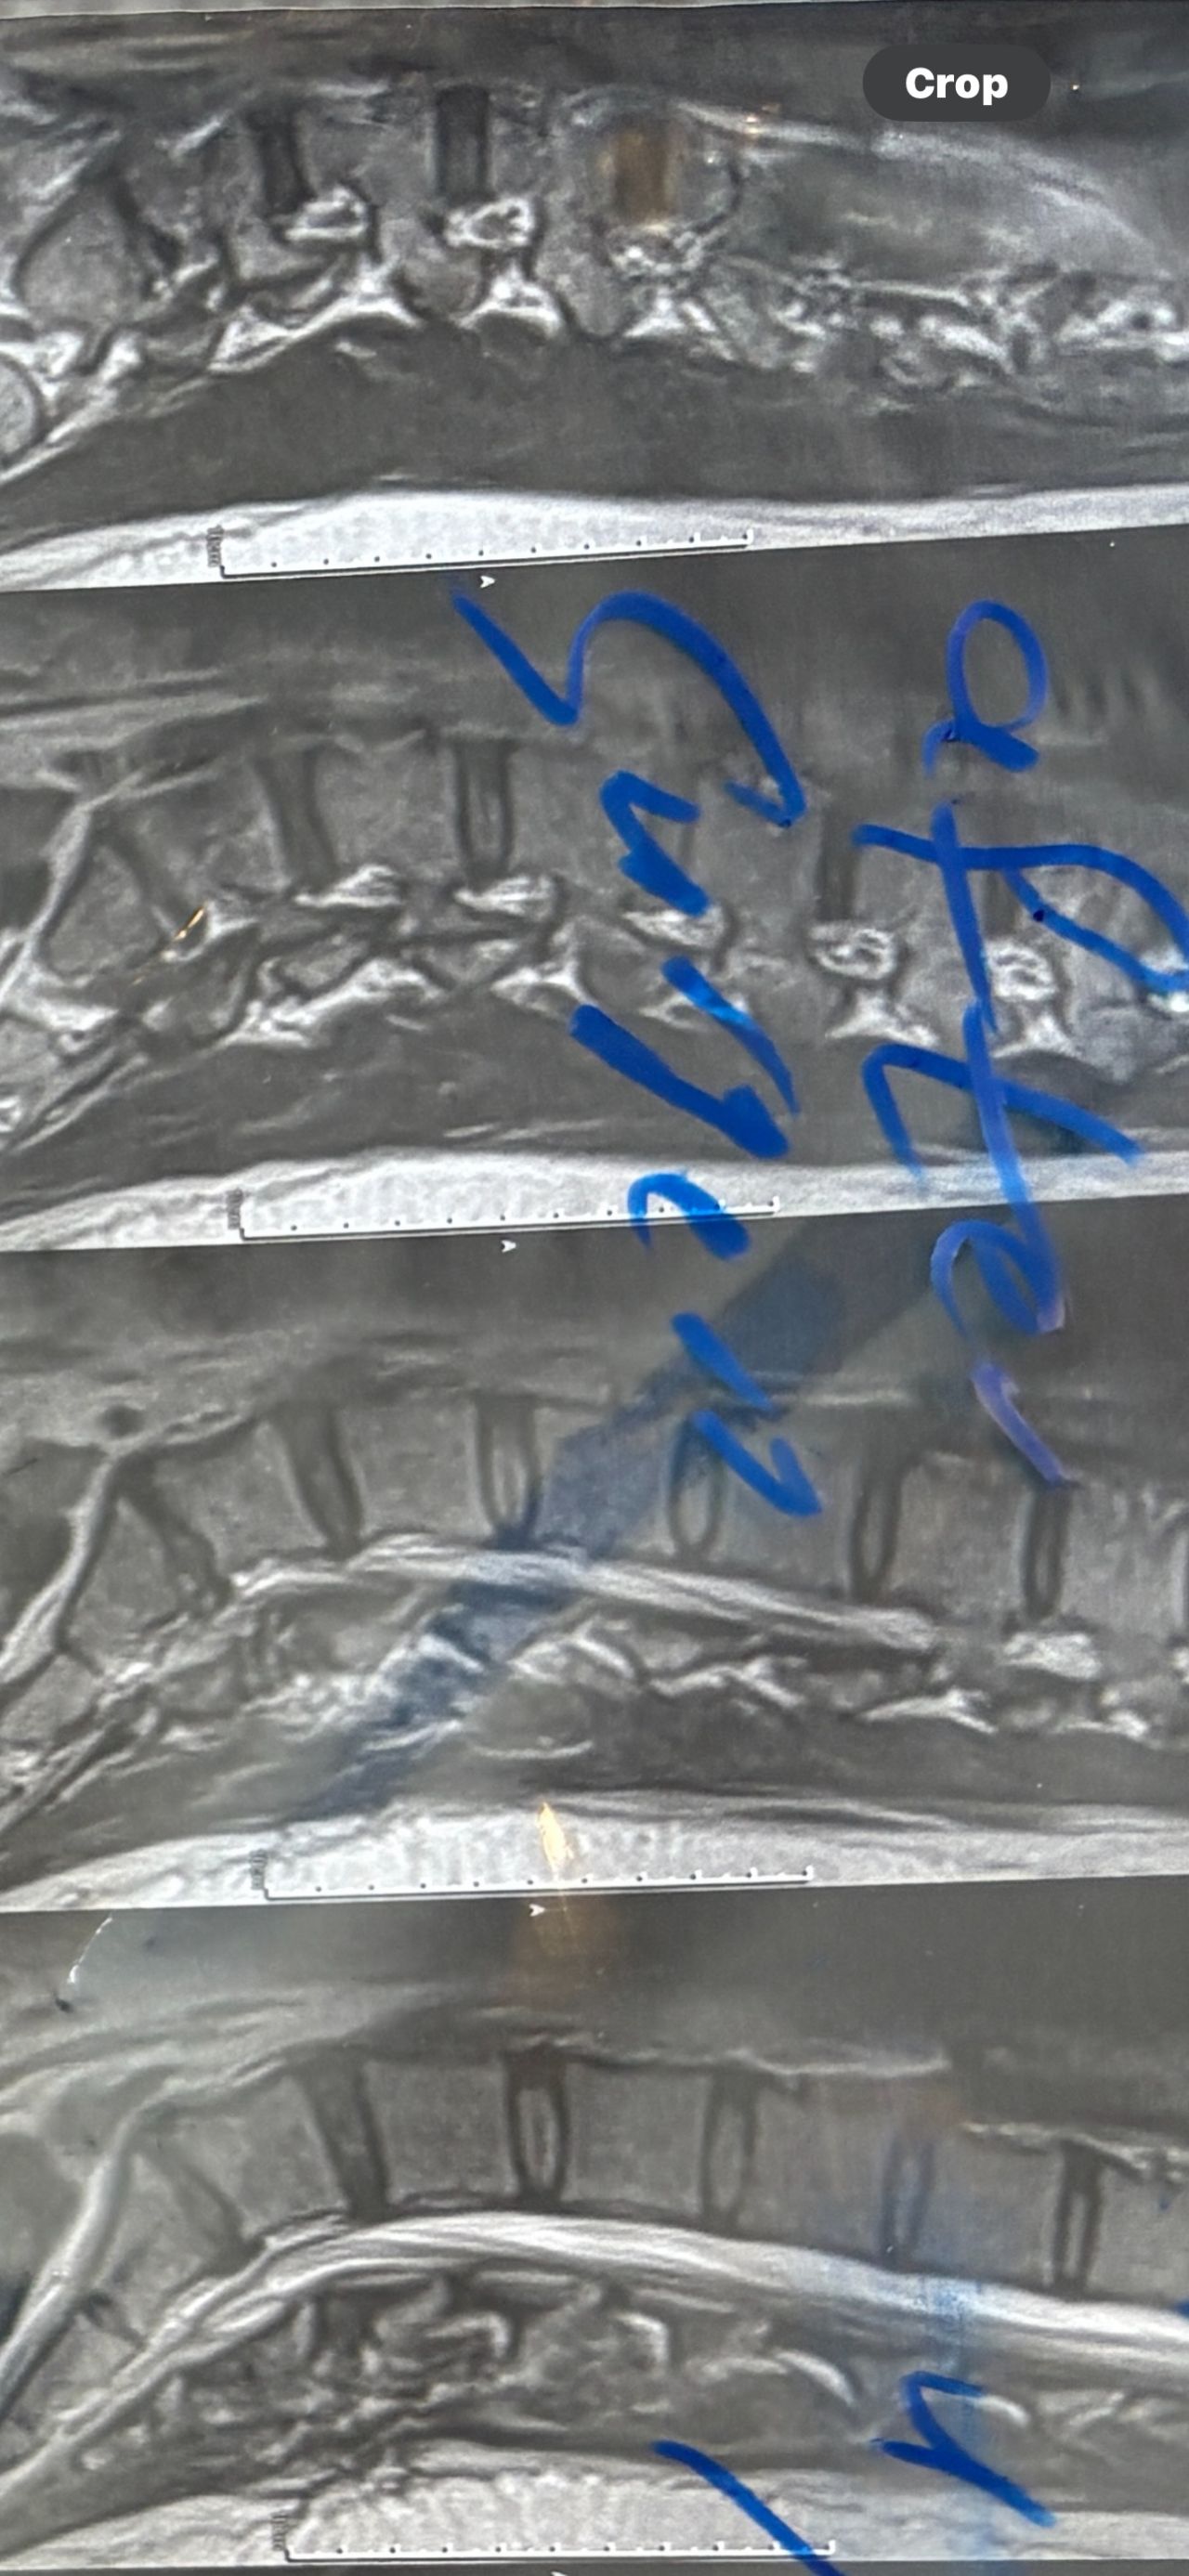

40 yrs old male patient presented to my office who had severe R gluteal pain and radicular pain along R L5-S1 now pain has reduced by 80% in his motor exam had R big toe L5 motor reduced to 4+\5 and R S1 DTR was 0 while L S1DTR was 1+

We did EMG/NCV which showed Mod- sever R L5 S1 irritation without any active axonal loss

I had to decide to refer him for surgery or not patient didn’t have any treatment meanwhile

I ordered new L/S mri

I posted his new mri and old mr

Which was 20 days ago and have posted all below

The first 12 mris had been done 20 days ago

After those first 12 MRIs i have posted new MRIs which were done yesterday

After seeing his new mri and emg/ncv and getting sure his neurological deficit is not active and progressing i told patient he doesn’t need surgery at this time and released him with some advices and exercises

Keep in mind when patient is 80-90 percent pain free and stable i would never give treatment to them just give exercises and follow up their condition